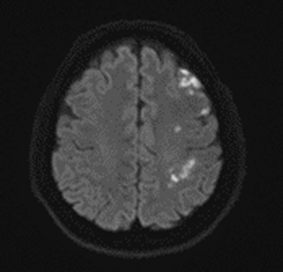

바로 당일 뇌 MRI 검사를 진행했습니다.

결과는... 좌측 급성 뇌경색이었어요 ㅜㅜ

그림14.png 촬영 일시: 2025.02.11

<Fig 1. 좌측 급성 뇌경색으로 진단된 뇌 mri 검사>

만약 그냥 목디스크 치료만 했다면 어떻게 됐을까요?

정말 상상하기도 싫습니다.

다행히 저희는 응급으로 분당서울대병원에 협진 의뢰를 드렸고

골든타임 내에 치료를 받으실 수 있었습니다.

지금은 회복 단계에 있으시다고 하니 정말 다행이에요.